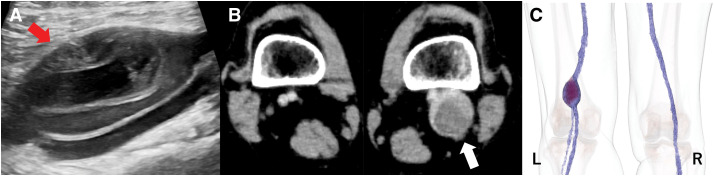

A 56-year-old woman with recurrent acute pulmonary embolism was diagnosed with a left popliteal venous aneurysm (PVA) by venous echocardiography. During anticoagulation therapy with heparin for acute pulmonary embolism, she was found to be positive for heparin-induced thrombocytopenia (HIT) antibodies. Surgery was performed with argatroban for anticoagulation, removal of the thrombus in the PVA, and suturing of the vein. Postoperatively, the popliteal vein showed shrinkage, and no recurrence of thromboembolism was observed. We report a case in which a patient with a PVA positive for HIT antibodies was successfully treated with PVA resection and anticoagulation therapy with argatroban.